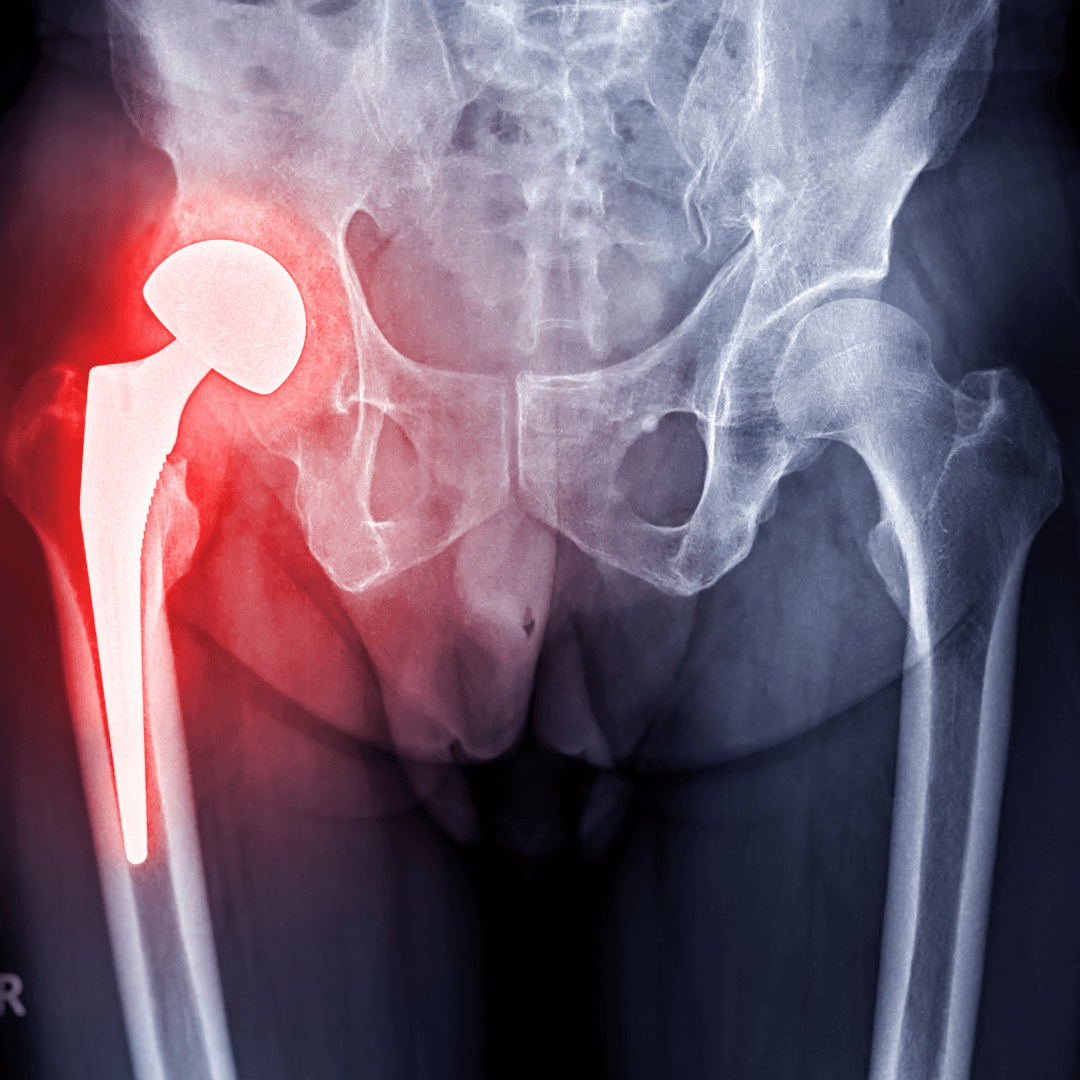

Our doctors assess your condition through a detailed physical exam and imaging (X-rays, MRI, etc.).

hip replacement surgery at vardaan laser gaya